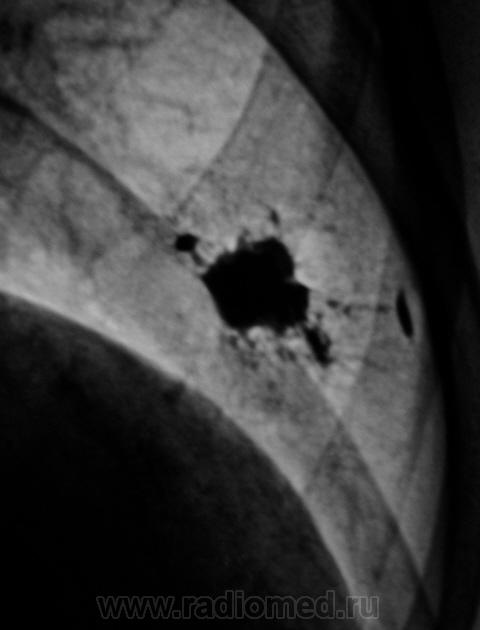

Рентгенограмма.

ТОМОГРАФИЯ.

Первый срез.